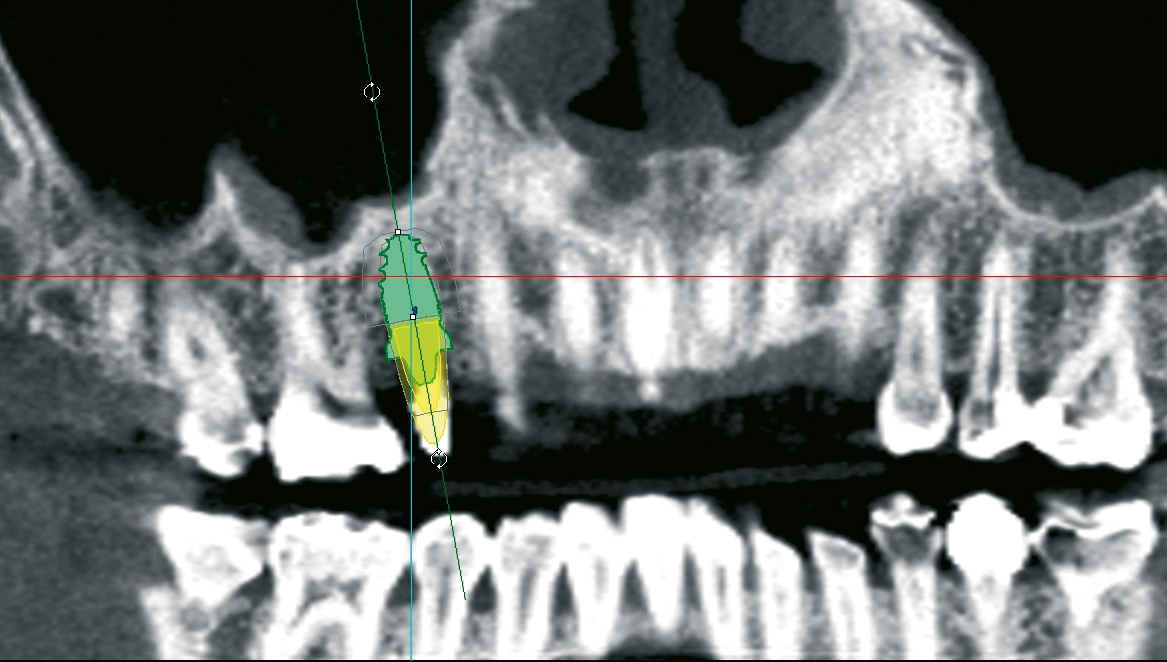

Um einen sinnvollen prothetischen Einschub unter optimaler Nutzung des Knochenangebots gewährleisten zu können, entschied man sich für eine teilnavigierte Aufbereitung des Implantatbetts. Mit der digitalen Planung sollte auch direkt nach der Implantatinsertion Primärstabilität gewährleistet werden, die für eine provisorische Sofortversorgung unerlässlich ist [8]. Als Implantat wurde das im Rahmen einer prospektiven, klinischen Langzeitstudie erprobte yttriumstabilisierte, einteilige Zirkondioxidimplantat ceramic.implant (vitaclinical, Bad Säckingen, Deutschland) ausgewählt, um der Patientin im Langzeitverlauf größtmögliche Sicherheit zu bieten. Das Implantat ist seit fünf Jahren dokumentiert und zeigt hier stabile Knochen- und Weichgewebsverhältnisse. Die Dreijahresdaten wurden bereits publiziert [9].

Um eine dreidimensionale Planung vornehmen zu können, wurde ein DVT erstellt und die Bilddaten wurden in die Planungssoftware 3Shape Implant Studio (3Shape, Kopenhagen, Dänemark) transferiert. Dort konnte die Implantation virtuell vorgenommen und in allen Raumdimensionen optimiert werden. Auf dieser Grundlage wurde eine Bohrschablone zur Teilnavigation hergestellt. Mittlerweile ist auch eine vollnavigierte, hülsenlose Implantation mit dem ceramic. implant möglich, das im Rahmen einer klinischen Studie eine noch präzisere Positionierung als bei den gängigen hülsengeführten Bohrschablonen zeigte [10].